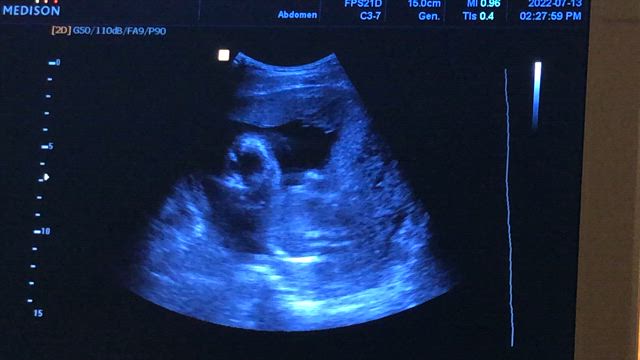

R先生④性別判定(3回目)※性別確定‼︎

2022年7月14日